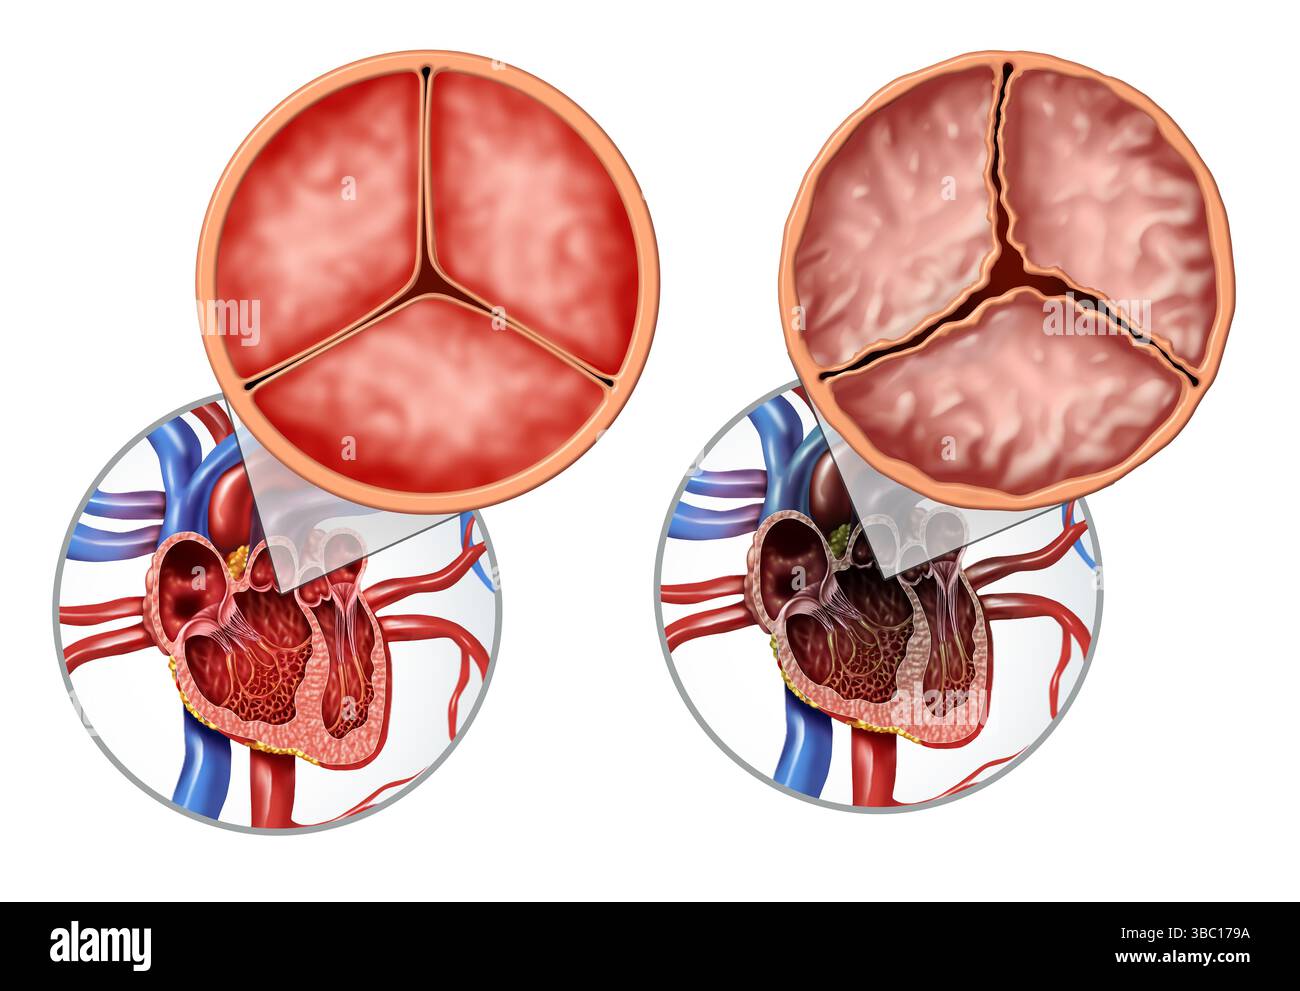

Aortic Valve disorder or valvular Disease as Human heart illness anatomy diagram and medical illustration concept Stock Photohttps://www.alamy.com/image-license-details/?v=1https://www.alamy.com/aortic-valve-disorder-or-valvular-disease-as-human-heart-illness-anatomy-diagram-and-medical-illustration-concept-image678607926.html

Aortic Valve disorder or valvular Disease as Human heart illness anatomy diagram and medical illustration concept Stock Photohttps://www.alamy.com/image-license-details/?v=1https://www.alamy.com/aortic-valve-disorder-or-valvular-disease-as-human-heart-illness-anatomy-diagram-and-medical-illustration-concept-image678607926.htmlRF3BC179A–Aortic Valve disorder or valvular Disease as Human heart illness anatomy diagram and medical illustration concept